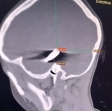

Gupta je Guardianu dostavila CT snimke djece s ranama na glavi. To je uključivalo osmogodišnju djevojčicu za koju je patolog opisao da pokazuje “ranu od metka u glavu koja ulazi s desne strane s metkom u mozgu (medijalni desni temporalni režanj)”.

Metak u glavi